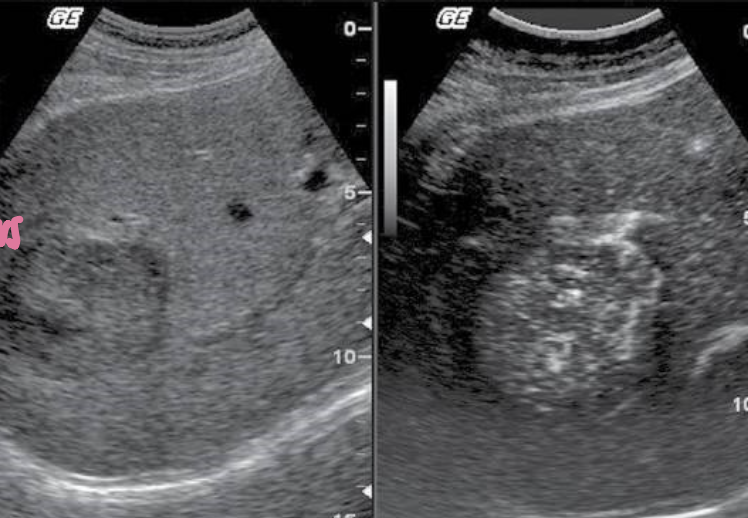

HCC (Hepatocellular Carcinoma) → most common primary malignant neoplasm of the liver

2D US: hypoechoic, echogenic, complex/heterogenous, usually solitary massive tumor, can be multiple nodules throughout the liver, diffuse infiltrative mass, ascites; **fibrolamellar carcinoma has same appearance, but in adolescents

color doppler: very vascular, vascular lumen invasion in both hepatic and portal veins

DDX: liver cell adenoma